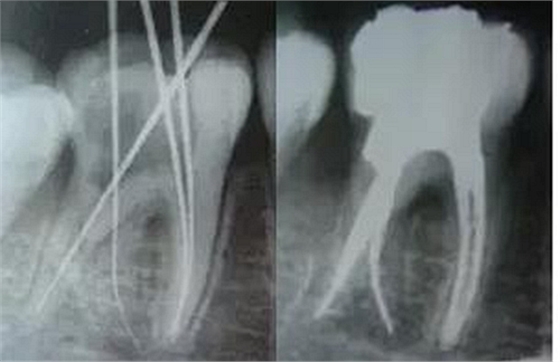

最后來玩一個根管治療質(zhì)量的評估——下圖是武大彭彬教授的一個病例,仔細觀察可以挑出一點問題,但問題事出有因!看看你的“眼力”如何——問題在那里?教授的專業(yè)水平是不用懷疑的,那么事出的原因可能是什么?

問題答案:這個病例的問題主要反應在開髓的洞形修整,注意觀察該牙X-RAY的左側(cè)洞壁,如果常規(guī)情況制備成這樣是由于裂鉆破壞了洞壁和洞底所形成的臺階。如果評估根管治療的質(zhì)量那是要扣分的!但這個病例仔細觀察洞壁形態(tài)就可以看出:該病例屬于再治療的病例,因此還是屬于一個理想的病例。